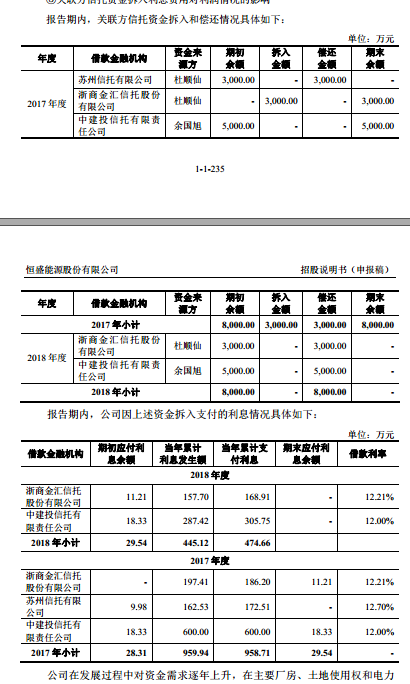

原标题:研究人员创造出一种3D打印的生物可吸收呼吸道支架 来源:cnBeta.COM

来自苏黎世联邦理工学院的研究人员创造了一种新的3D打印气道支架,这种支架是可以被生物吸收的。他们认为这种新型支架可以简化未来上气道阻塞的治疗,特别是因损伤或疾病导致的气管或主支气管狭窄。这种类型的损伤或疾病可能会导致死亡,因为它会限制人进入大脑的氧气量。

今天,外科医生使用硅胶或金属制成的支架作为治疗这些病人的一种方法。然而,金属支架在不再需要时必须通过手术移除,增加感染和手术困难的可能性,刚性较差的硅胶支架可能会从插入部位移位,这都是非常让人不愿意看到的。

研究人员表示,这是因为植入物不适应患者的解剖结构,而开发的新支架是专门为患者量身定做的,并且是可生物吸收的,可生物吸收特性对于医疗器械而言非常有实用意义,因为它可以让支架在植入后逐渐溶解。

用于创建支架的3D打印过程被称为数字光处理,并使用专门为此目的调整的光敏树脂。该过程要求研究人员创建一个特定部分气道的计算机断层扫描图像,在将数据传输到DLP打印机之前,该图像用于开发支架的3D模型。

从打印机上照射的紫外光使树脂硬化,逐层构建支架。新建造出来的的树脂在室温下通常会太厚,需要在70至90摄氏度的温度下进行处理,然后需要一个特殊的工具来辅助安装,因为它们必须被折叠。植入物不能打结,也不能挤错方向,要精确地在目标位置展开。